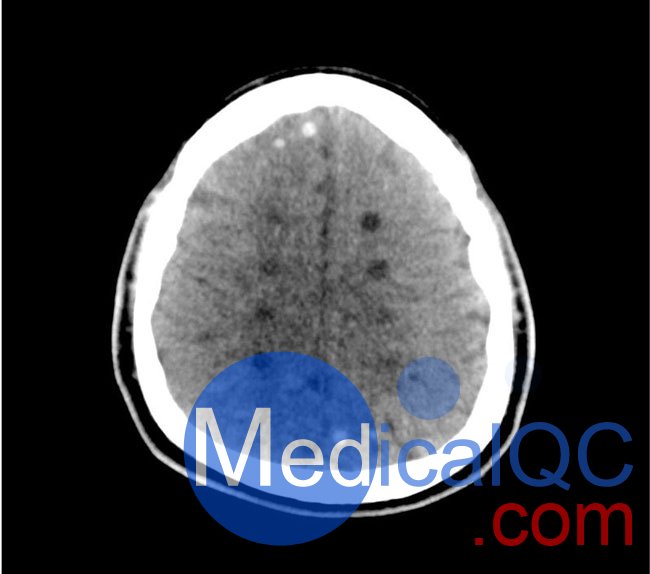

50-01頭部CT模體,50-01腦中風(fēng)頭部模體,50-01腦出血頭部模體模擬了具有中風(fēng)和出血模式的頭部。它覆蓋枕骨大孔的頂點(diǎn)。

卒中模式包括早期梗死的體征(大腦中動(dòng)脈高密度、基底神經(jīng)節(jié)消失)、急性和亞急性分水嶺梗死以及不同年齡的腔隙性梗死。

出血模式包括蛛網(wǎng)膜下腔出血、不同年齡的硬膜下出血、腦室內(nèi)出血和腦出血。

• 高密度大腦中動(dòng)脈 (MCA) 和左側(cè)基底神經(jīng)節(jié)消失

• 大腦中/后動(dòng)脈 (MCA/PCA) 和大腦前動(dòng)脈/中動(dòng)脈 (ACA/MCA) 領(lǐng)域的分水嶺梗死

• 8 個(gè)不同年齡的腔隙性梗死

出血

• 蛛網(wǎng)膜下腔出血(2個(gè)地區(qū))

• 不同年齡的硬膜下出血(3個(gè)地區(qū))

• 腦室內(nèi)出血(左側(cè)腦室)

• 腦出血(2 個(gè)丘腦,6 個(gè)皮質(zhì)下)

50-01頭部CT模體,50-01腦中風(fēng)頭部模體,50-01腦出血頭部模體影像效果圖: